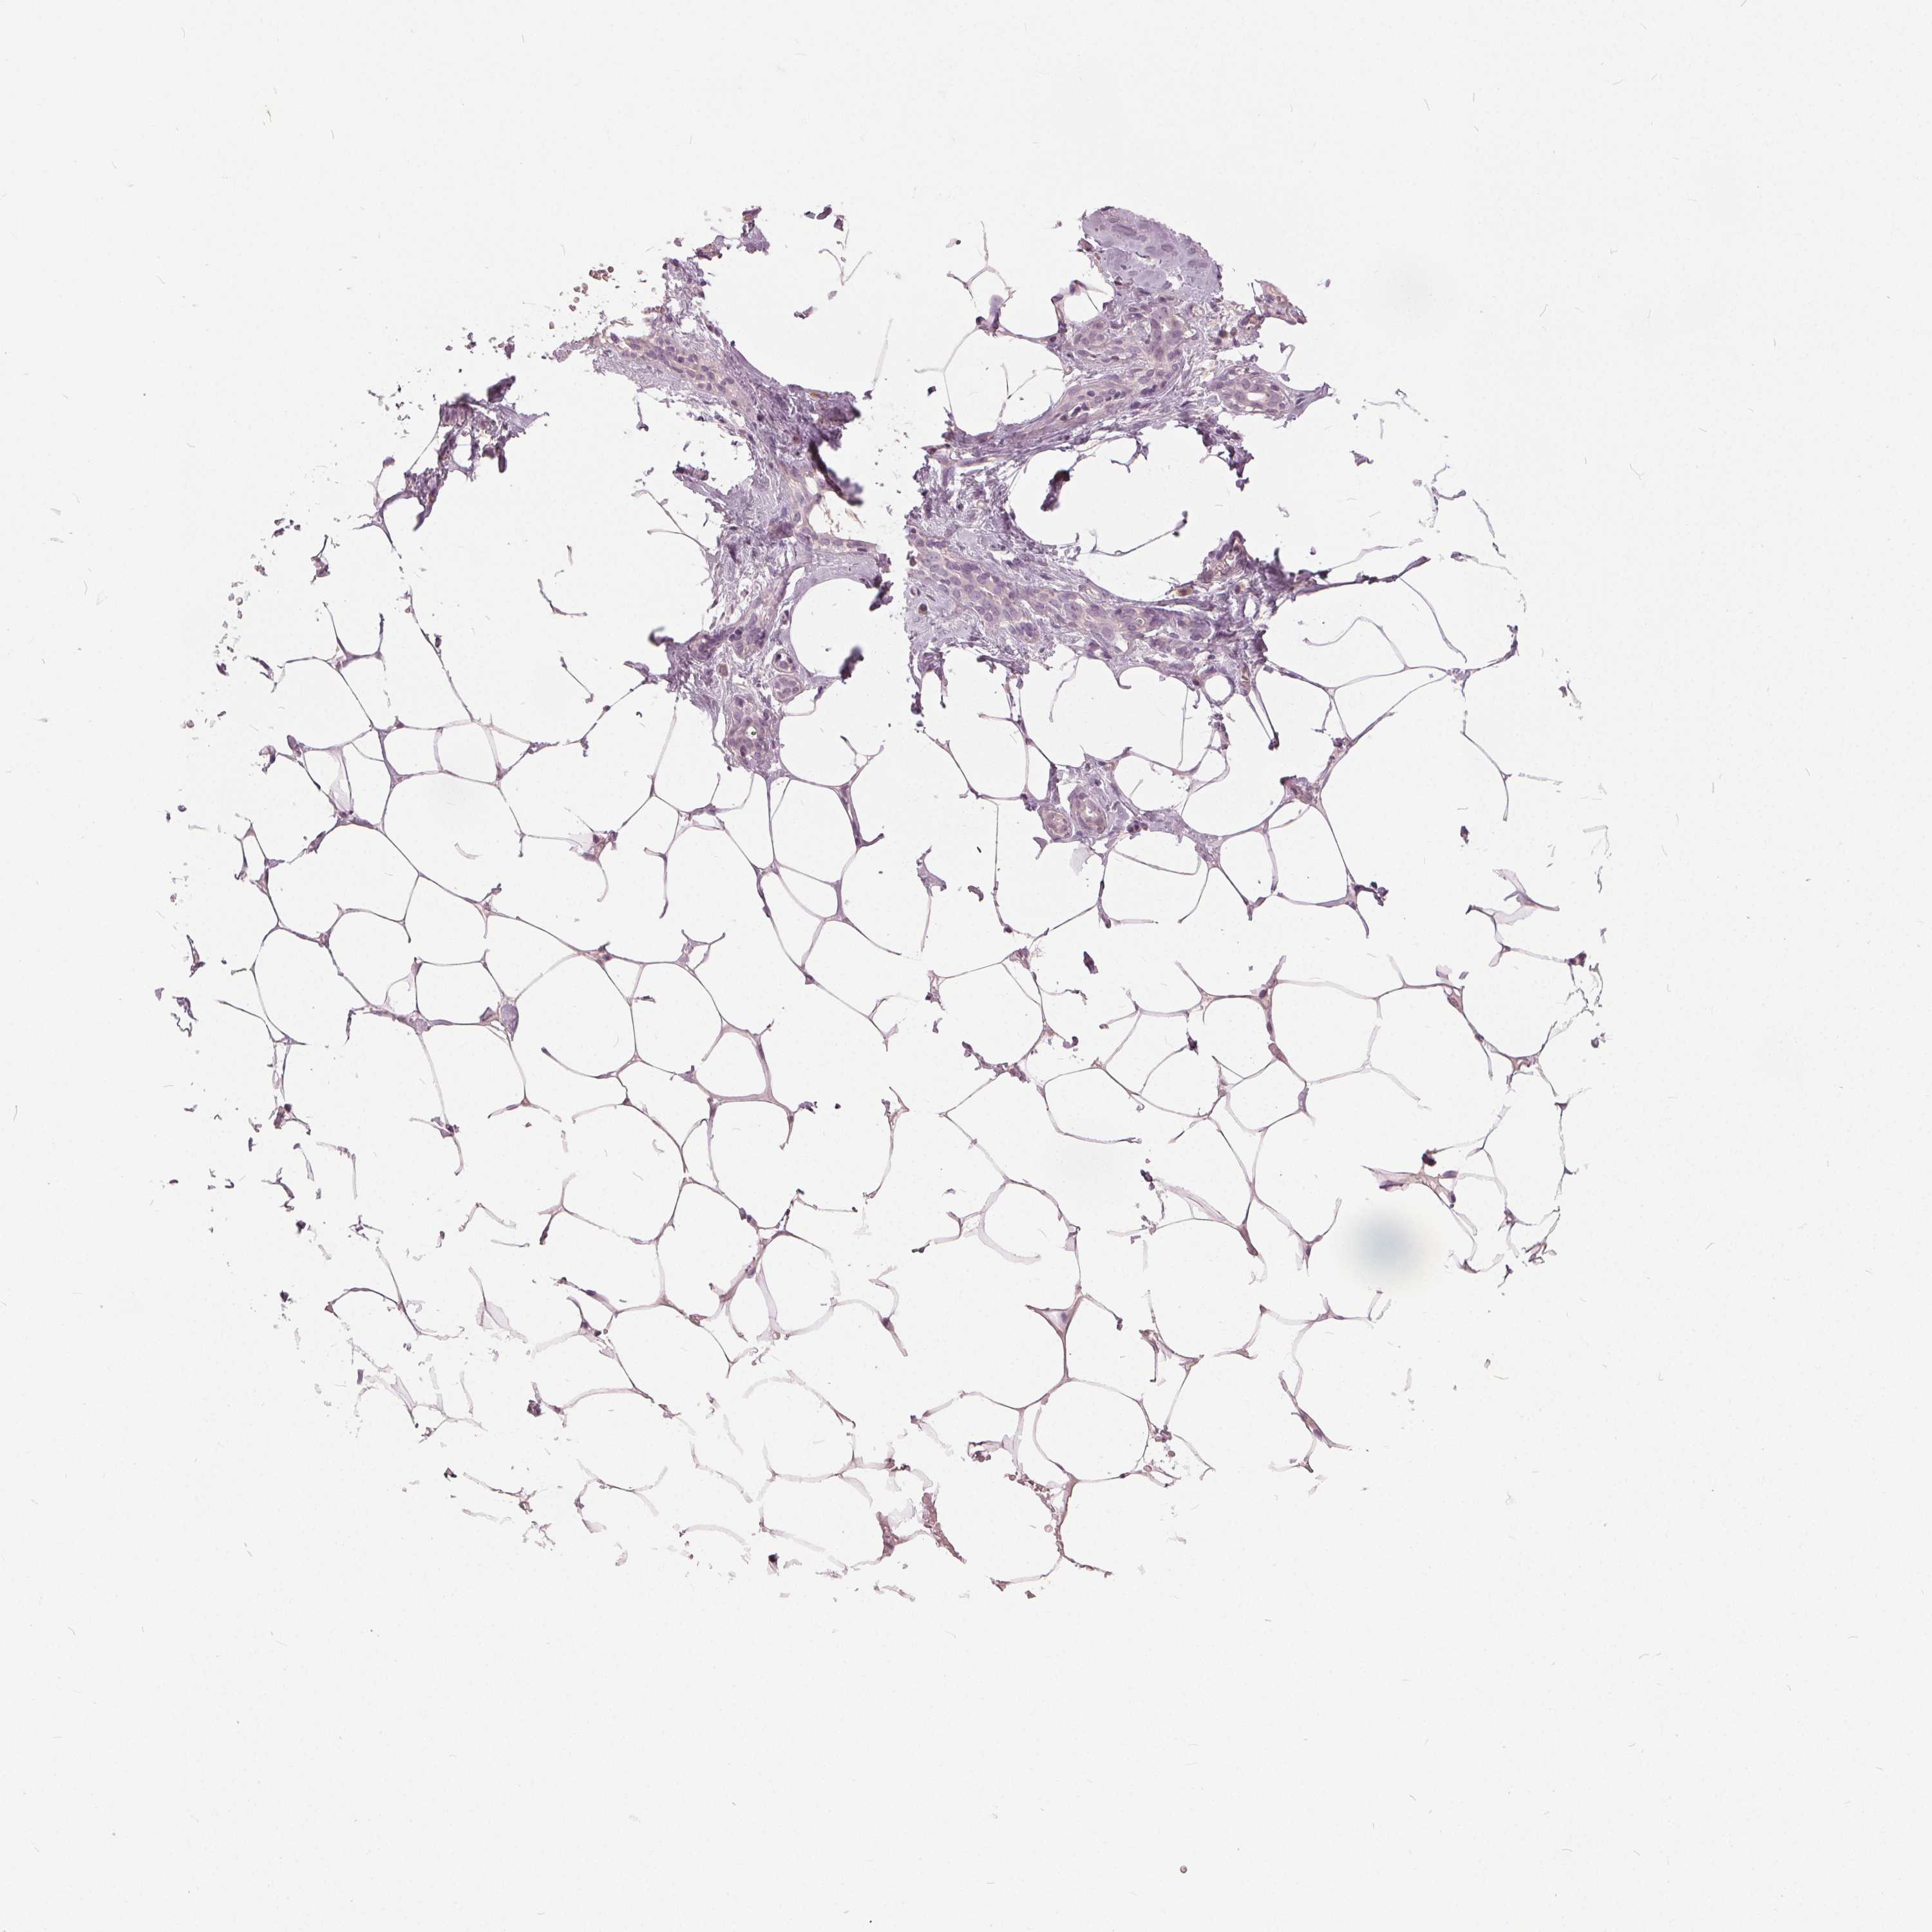

BREAST - Antibody stainingi

Antibody staining in the annotated cell types in the current human tissue is reported as not detected, low, medium, or high, based on conventional immunohistochemistry profiling in selected tissues. This score is based on the combination of the staining intensity and fraction of stained cells.

Each image is clickable and will lead to virtual microscopy that enables deeper exploration of all samples and also displays staining intensity scores, fraction scores and subcellular localization as well as patient and tissue information for each sample.

Antibody HPA062136

Adipocytes Not detected

Glandular cells Not detected

Myoepithelial cells Not detected